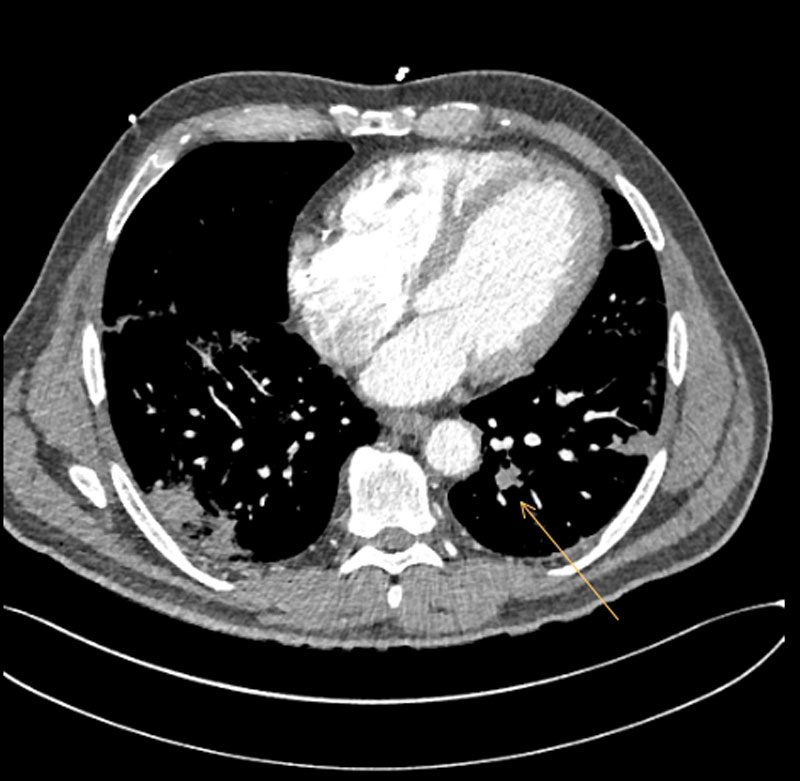

On day 10, following a respiratory deterioration requiring oxygenation with 15 l/min delivered via a face mask with reservoir, the patient was transferred to our intensive care unit (ICU). After an initial early peak, CRP had at this point fallen to 79.5 mg/l although D-dimer levels were now 6.62 mg/l with a fibrinogen of 5.9 g/l. Given the respiratory deterioration, despite apparent improvement in laboratory markers of inflammation, we elected to perform a computed tomography (CT) examination of the thorax with a pulmonary angiogram to assess for parenchymal complications of infection (such as abscess, empyema) and rule out a macrovascular thromboembolism. This examination demonstrated filling defects in the left upper lobe, right upper lobe and right middle lobe pulmonary arteries extending to the segmental arteries consistent with bilateral paracentral pulmonary embolism, and in addition widespread peripheral pneumonic infiltrates consistent with the diagnosis of COVID-19 [6] in all lobes (fig. 2).

Figure 2 Computed tomography pulmonary angiogram demonstrating pulmonary embolism 10 days after admission.